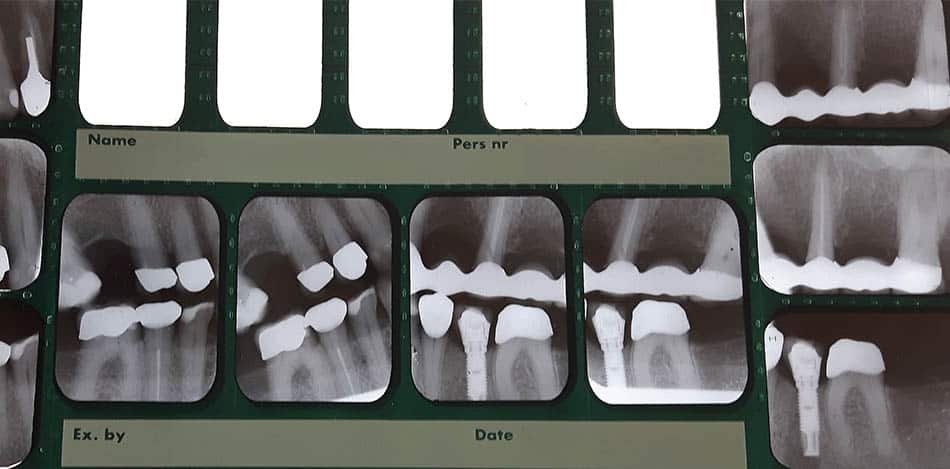

För att få ett tandvårdskort krävs att man har extra stort behov av tandvård. Det kan till exempel bero på att man äter antidepressiva eller antipsykotiska preparat. Kortet gäller för undersökningar, förebyggande vård, lagningar, behandling av tandlossningssjukdom, rotfyllningar, utdragning av tänder och avtagbara proteser. Däremot ingår inte fasta proteser som kronor, broar och implantat.